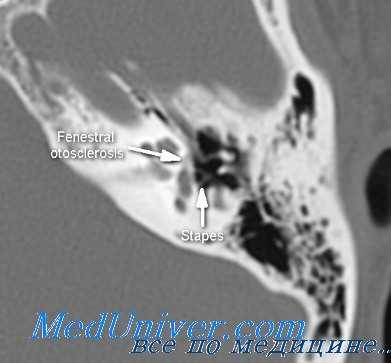

(Слева) При аксиальной КТ правой височной кости у молодого взрослого с прогрессирующей кондуктивной тугоухостью визуализируется типичная отоспонгиозная бляшка (фенестральный отосклероз) спереди от овального окна в области предполагаемой локализации щели перед окном.